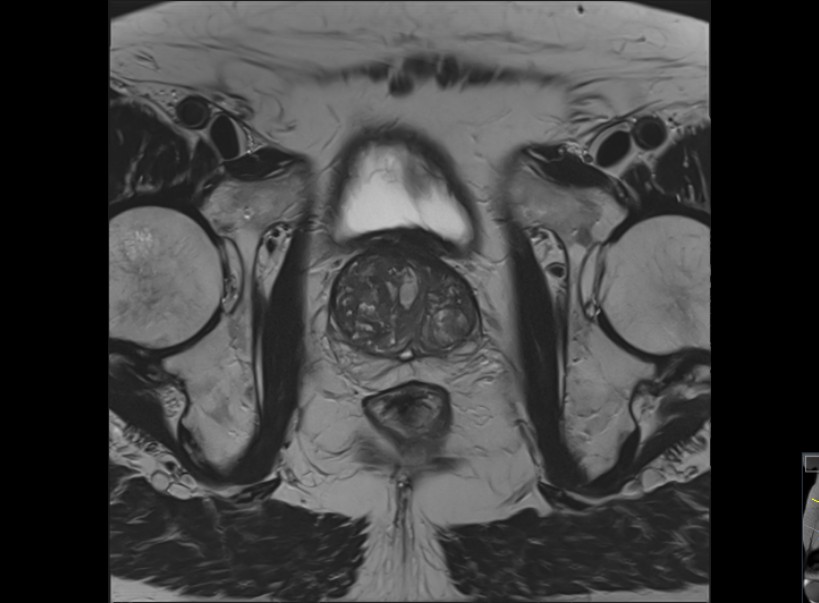

Die Prostata-Magnetresonanztomographie (Prostata-MRT) ist ein präzises und strahlenfreies Diagnoseverfahren zur Untersuchung der Prostata. Sie bietet detaillierte Aufnahmen, die bei Verdacht auf Prostataveränderungen oder zur Überwachung hilfreich sein können. Die Prostata-MRT wird oft ergänzend zur PSA-Wert-Messung oder bei auffälligen Tastbefunden empfohlen.

Die Prostata-MRT ist besonders präzise und ermöglicht es, Veränderungen innerhalb des Prostatagewebes frühzeitig zu erkennen. Mit ihr lassen sich auch mögliche Biopsien (Gewebeentnahme) zur Diagnosesicherung viel exakter planen und durchführen. Da die MRT-Untersuchung strahlenfrei ist, belastet sie den Körper nicht unnötig mit Röntgenstrahlen.